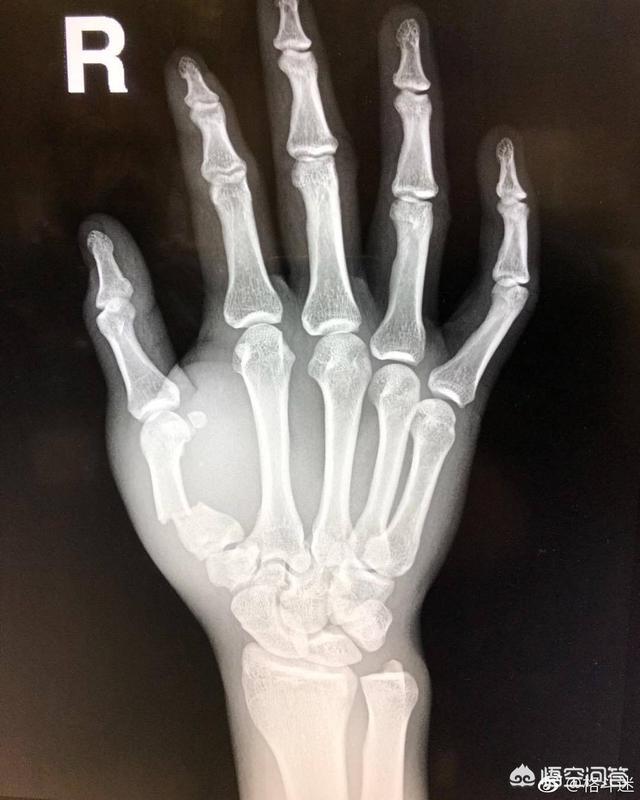

如上图所示,这种骨折最经常发生在第4或第5掌骨颈,偶尔也会发生在第1掌骨基底。因为实在太常见了,所以在骨科这种骨折还有个专门的名称叫“Boxer's Fracture”,即“拳击手骨折”。听这名字,你就懂了。。。

之所以会这样,主要的原因是:相对于人体坚固的颅骨和下颌骨,人手的掌骨其实非常细且脆弱。

一拳打在下巴上,被击打者很容易直接被KO失去意识。这个表象让人们觉得好像下巴或头部很脆弱,其实并不是这样的。被KO,并不是因为颅骨或下颌骨骨头本身脆弱,而是因为脆弱的大脑因为击打的力量,在颅骨中震荡损伤引起的。脆弱的是大脑,而前额的颅骨和下巴的下颌骨是非常坚硬的。

而相比之下,手部的掌骨其实非常细小且脆弱的,这也是为什么必须要用缠手带和拳套来保护拳峰和手骨。如果没有带拳套等保护措施,直接用裸拳去击打头面部,反作用力很容易引起骨折。毕竟,经过训练懂得出拳的人一拳出去的力量,反作用回来真的很容易引起手部骨折,尤其是和对手距离控制不好,手部着力点有偏差时……